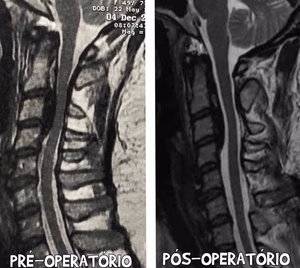

Caso cirúrgico: Cifose congênita operado pela equipe do Dr Antônio Prates.